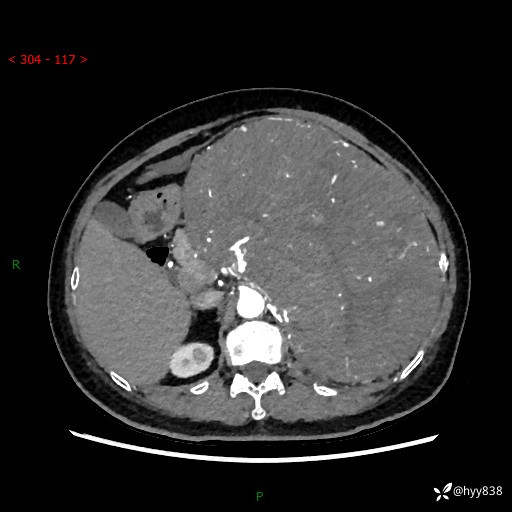

据说只有腹膜后,才能见到如此巨大的肿块---(有结果)

主诉:发现腹膜后占位1周

简要病史:患者1周前因头晕在当地第二人民医院检查发现左侧腹膜后区巨大富血供占位性病变,患者自诉腹部稍硬,无其他不适,无血尿,无腰痛等不适,患者为求进一步治疗来我院,门诊以“腹膜后占位性病变”收入我科。 起病以来,患者精神、饮食、睡眠可,大便正常,小便如上述,体力体重无明显改变。

临床诊断:腹膜后占位

腹部CT增强(动脉期+静脉期 ) ---平扫外院